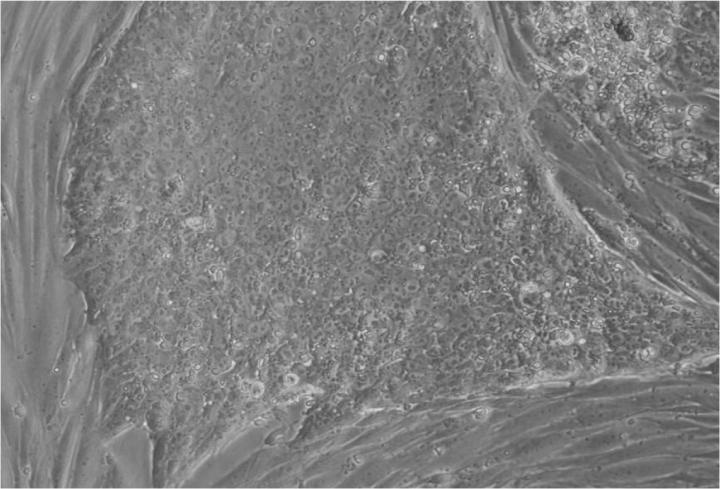

人類胚胎干細(xì)胞 (ESC) 是從囊胚(一種非常早期的人類胚胎)中發(fā)現(xiàn)的少量細(xì)胞產(chǎn)生的。從囊胚中取出的單個(gè)細(xì)胞生長成大量細(xì)胞以產(chǎn)生 ESC“系”。

胚胎干細(xì)胞的自我復(fù)制能力允許從干細(xì)胞系中培養(yǎng)出大量細(xì)胞,并與全球?qū)嶒?yàn)室共享多年,從而最大限度地減少了從囊胚制造新胚胎干細(xì)胞的需求。

胚胎干細(xì)胞研究的重點(diǎn)是干細(xì)胞系。這些是細(xì)胞群,都攜帶相同的基因,在實(shí)驗(yàn)室中通過許多代細(xì)胞的許多生長和分裂周期生長。一個(gè)細(xì)胞系可以為許多研究人員提供大量細(xì)胞。

Jenny Nichols 拍攝的人類囊胚和人類胚胎干細(xì)胞圖像。愛丁堡大學(xué) MRC 再生醫(yī)學(xué)中心向 SCNT 和多莉羊注射細(xì)胞核。